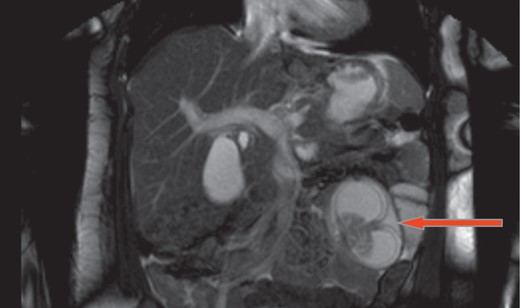

A 37-year-old 6 weeks pregnant female status post-LRYGB 2 years ago presented with 4 hours history of sudden onset of epigastric and peri-umblical pain and tenderness, associated with nausea and vomiting. Vitals signs were stable. Labs including white blood cell count, serum chemistry, urinalysis and liver function tests were all within normal limits. Abdominal ultrasound confirmed intrauterine pregnancy. Magnetic resonance imaging revealed intussusception of small bowel with close loop obstruction (Figs. 1 and 2). Following initial resuscitation, emergent laparoscopy was performed which confirmed the diagnosis. Intra-operatively significantly dilated loop of jejunum approximately 20 cm in length was noticed close to the jejuno-jejunostomy with retrograde telescoping of the jejunum (Fig. 3). At that time decision was made to covert to open laparotomy with resection of irreducible intussusception and reconstruction of jejuno-jejunostomy (Fig. 4). Post-operative course was uneventful, the patient subsequently recovered fully and was discharged home on post-operative day 4. On follow-up, patient was seen in the clinic and reported doing well and pain free. Patient also was following up with her obstetrician to assess the viability of the fetus.

Magnetic resonance imaging shows intussusception of small bowel with close loop obstruction (coronal view).